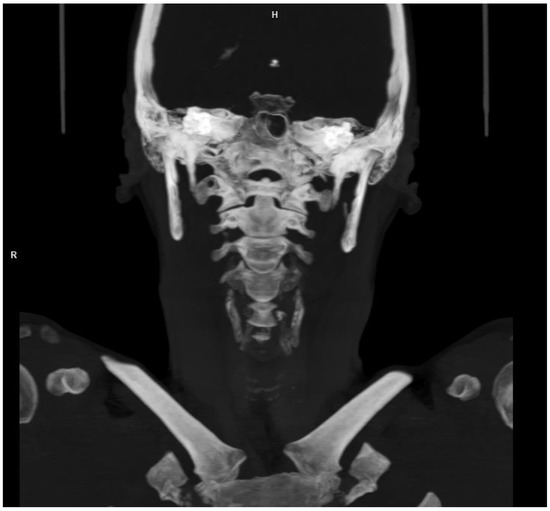

2.2. Diagnosis